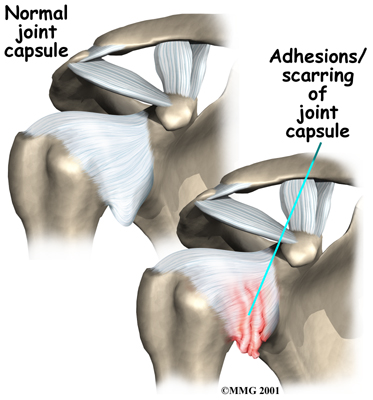

The terms frozen shoulder and adhesive capsulitis are often used interchangeably. In other words, the two terms describe the same painful, stiff condition of the shoulder no matter what causes it. A more accurate way to look at this is to refer to true adhesive capsulitis (affecting the joint capsule) as a primary adhesive capsulitis.

As the name suggests, adhesive capsulitis affects the fibrous ligaments that surround the shoulder forming the capsule. The condition referred to as a frozen shoulder usually doesn't involve the capsule. Secondary adhesive capsulitis (or true frozen shoulder) might have some joint capsule changes but the shoulder stiffness is really coming from something other than the joint capsule. Some of the conditions associated with secondary adhesive capsulitis include rotator cuff tears, biceps tendinitis, and arthritis. In either condition, the normally loose parts of the joint capsule stick together. This seriously limits the shoulder's ability to move, and causes the shoulder to relatively freeze.

As the name suggests, adhesive capsulitis affects the fibrous ligaments that surround the shoulder forming the capsule. The condition referred to as a frozen shoulder usually doesn't involve the capsule. Secondary adhesive capsulitis (or true frozen shoulder) might have some joint capsule changes but the shoulder stiffness is really coming from something other than the joint capsule. Some of the conditions associated with secondary adhesive capsulitis include rotator cuff tears, biceps tendinitis, and arthritis. In either condition, the normally loose parts of the joint capsule stick together. This seriously limits the shoulder's ability to move, and causes the shoulder to relatively freeze.

The shoulder is made up of three bones: the scapula (shoulder blade), the humerus (upper arm bone), and the clavicle (collarbone). The joint capsule is a watertight sac that encloses the joint and the fluids that bathe and lubricate it. The walls of the joint capsule are made up of ligaments. Ligaments are soft connective tissues that attach bones to bones. The joint capsule has a considerable amount of slack (loose tissue), so the shoulder is unrestricted as it moves through its large range of motion. As the name suggests, adhesive capsulitis affects the fibrous ligaments that surround the shoulder forming the capsule. The condition referred to as a frozen shoulder usually doesn't involve the capsule. Secondary adhesive capsulitis (or true frozen shoulder) might have some joint capsule changes but the shoulder stiffness is really coming from something other than the joint capsule. Some of the conditions associated with secondary adhesive capsulitis include rotator cuff tears, biceps tendinitis, and arthritis. In either condition, the normally loose parts of the joint capsule stick together. This seriously limits the shoulder's ability to move, and causes the shoulder to relatively freeze.

As the name suggests, adhesive capsulitis affects the fibrous ligaments that surround the shoulder forming the capsule. The condition referred to as a frozen shoulder usually doesn't involve the capsule. Secondary adhesive capsulitis (or true frozen shoulder) might have some joint capsule changes but the shoulder stiffness is really coming from something other than the joint capsule. Some of the conditions associated with secondary adhesive capsulitis include rotator cuff tears, biceps tendinitis, and arthritis. In either condition, the normally loose parts of the joint capsule stick together. This seriously limits the shoulder's ability to move, and causes the shoulder to relatively freeze.